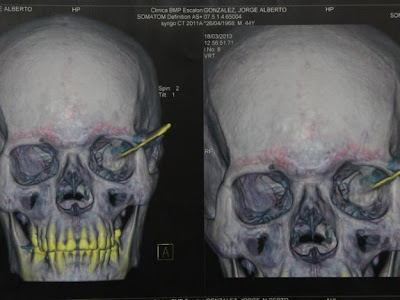

Ele fez uma viagem ao Panama,quando voltou descobriu algo estranho em sua cabeça!

1. Depois de visitar o Panamá, esse cara, sem saber, trouxe para casa um parasita enterrado em seu couro cabeludo.

2. A criatura viveu em sua cabeça por um mês !

3. Usando uma pinça, eles conseguiram puxar o parasita fora.

Aparentemente, é uma larva .Basta olhar o quão grande essa coisa é. Veja as imagens...